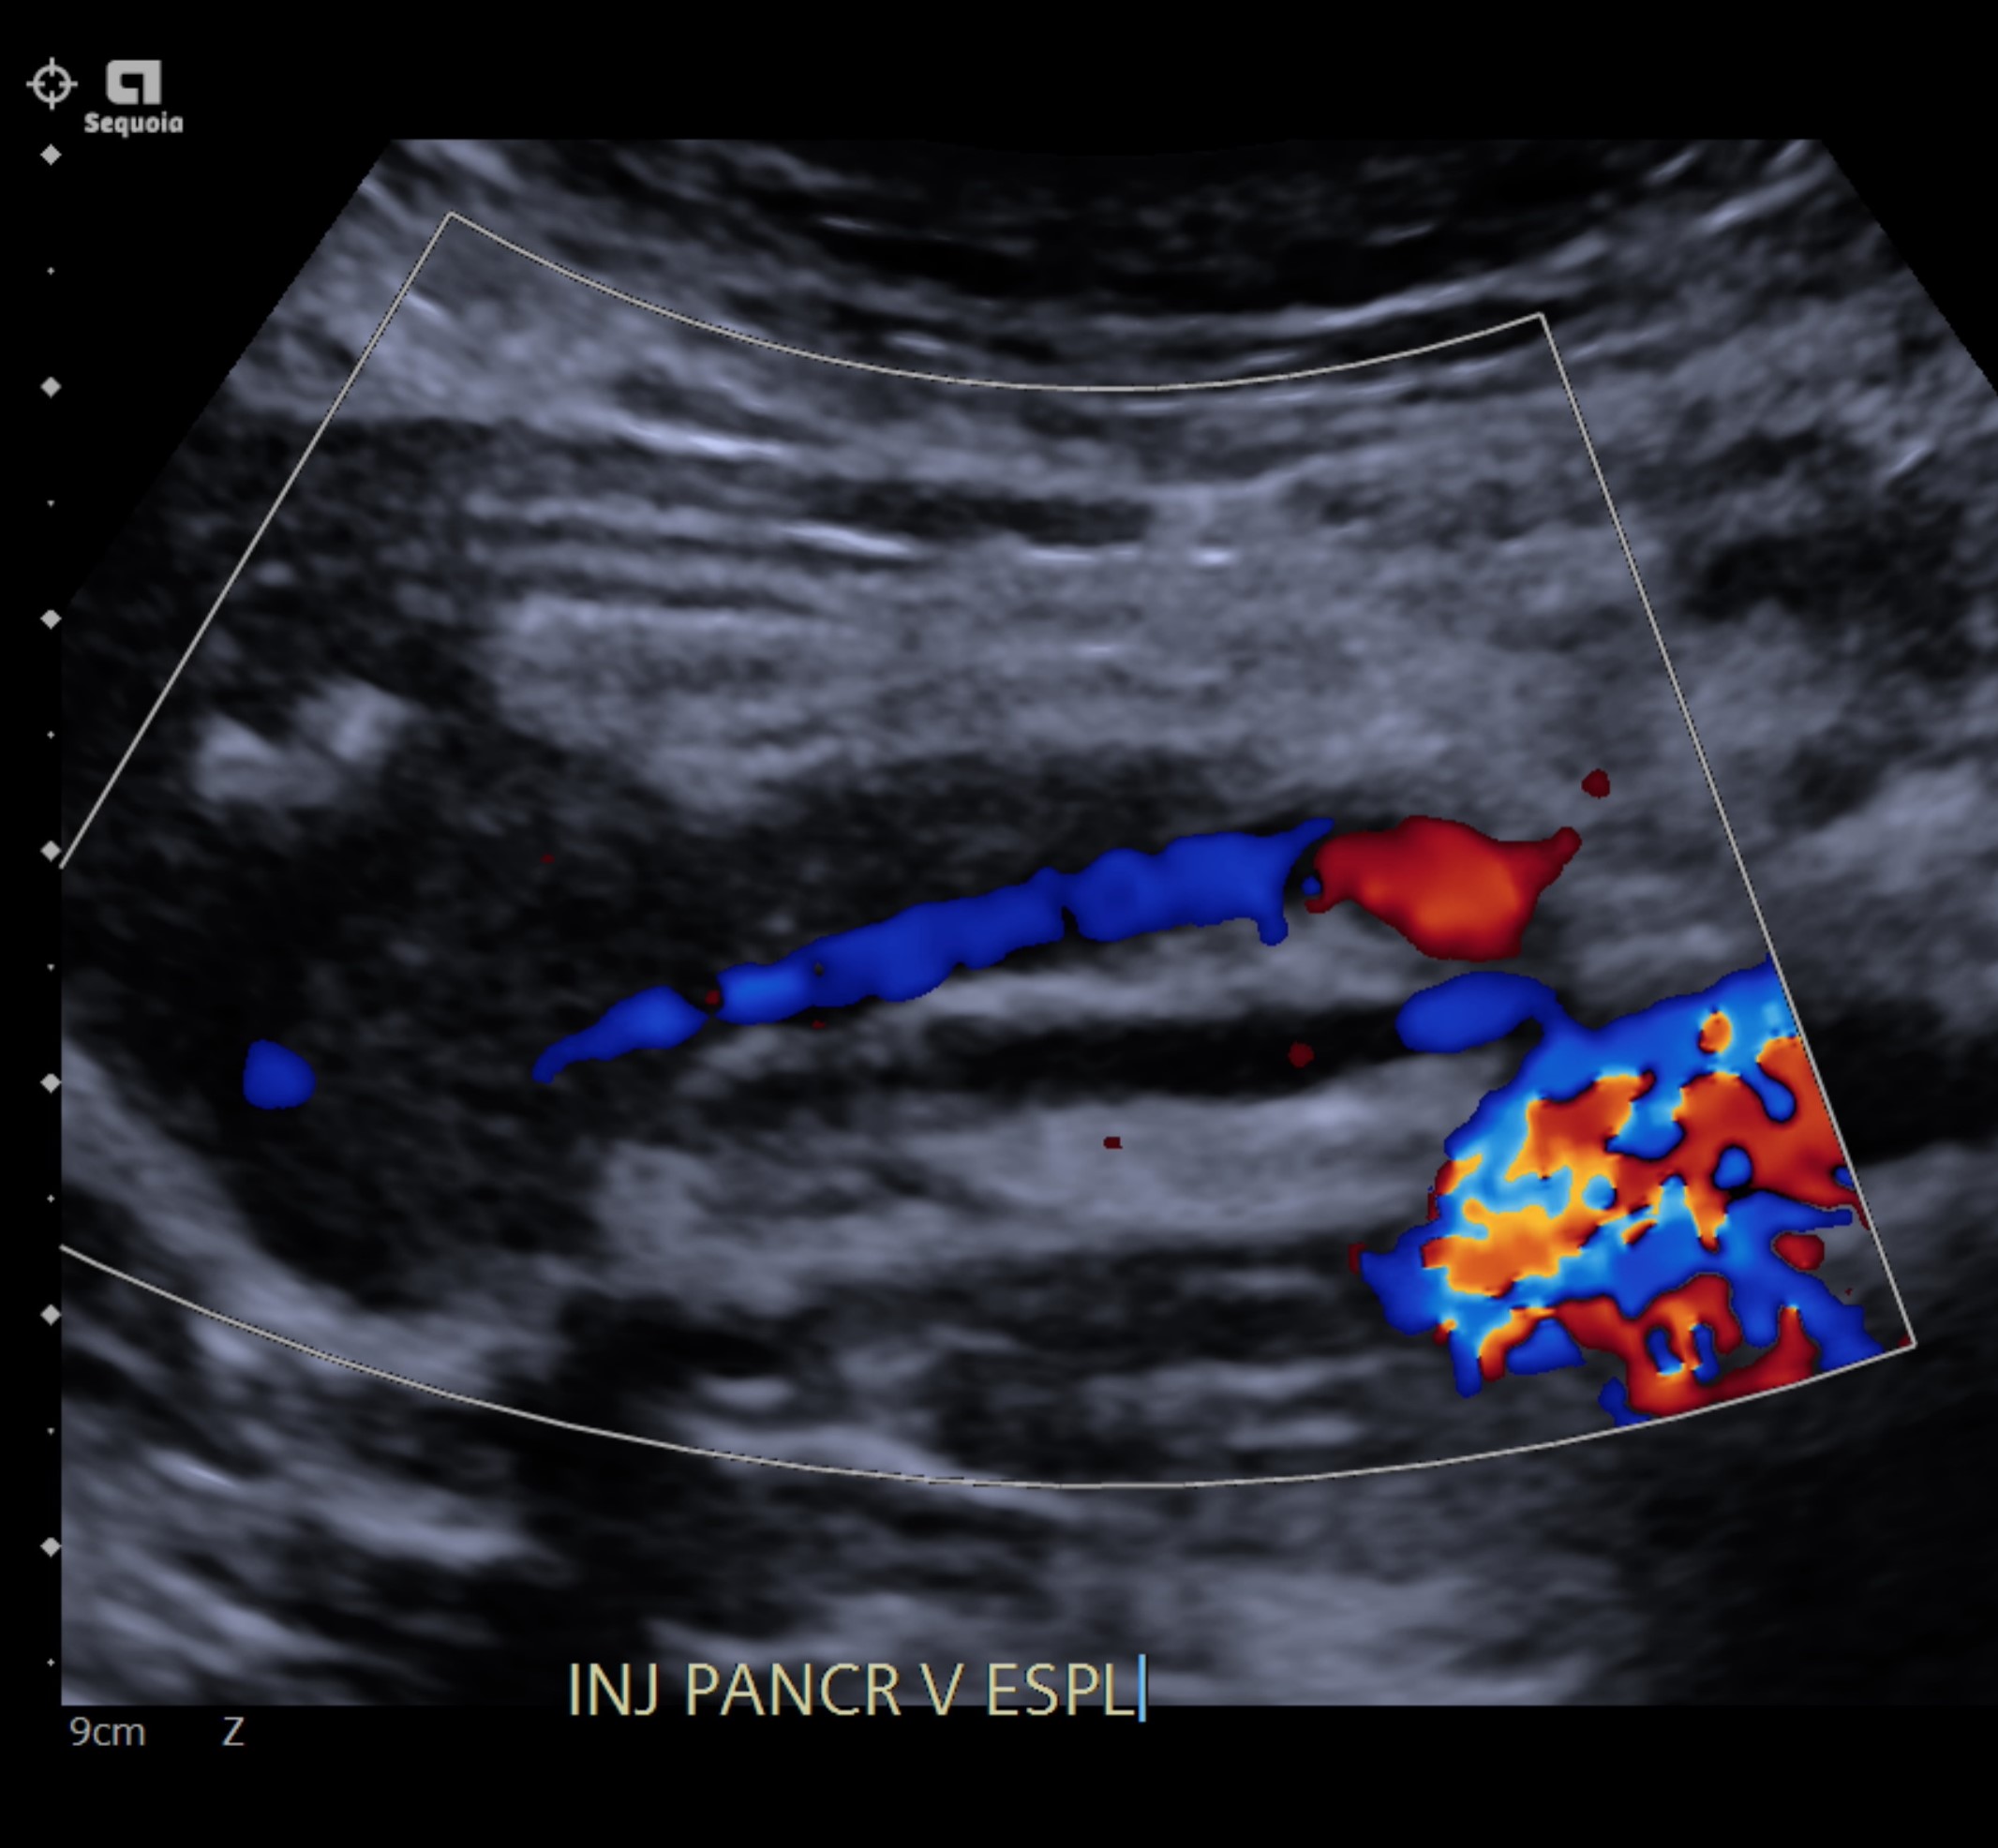

Case Report: A 20-year-old woman with an history of total pancreatectomy performed previously in 2015 for a giant solid pseudopapillary neoplasm was placed on the national waiting list for a pancreas transplant alone (PTA) in 2020 after completing 5-years of oncology follow up. The patient underwent a deceased-donor PTA in October 2022. Pancreatic venous drainage was achieved with primary anastomosis of the donor’s portal vein to the recipient's inferior cava vein, with no venous extension graft. Following our protocol, doppler ultrasonography was performed on the 1st postoperative day, revealing partial thrombosis of graft’s splenic vein. She was placed on continuous heparin infusion with no progression of splenic vein thrombosis. She was discharged on the 8th postoperative day with rivaroxaban plus aspirin. However, 30 days after pancreas transplant, she presented abdominal pain and increased amylase level. Computer tomography angiography revealed complete splenic vein thrombosis and partial portal vein thrombosis. Direct venography was performed through the internal jugular vein. Percutaneous mechanical thrombectomy was performed using Angioject catheter (6F hydrodynamic device). The lysis of the thrombus and restoration of flow in the splenic vein and portal vein was documented on immediate follow up direct venography.

The patient was discharged on the 4th postoperative day with apixaban and aspirin. At 3 months follow up, Doppler EUS revealed no graft thrombosis.